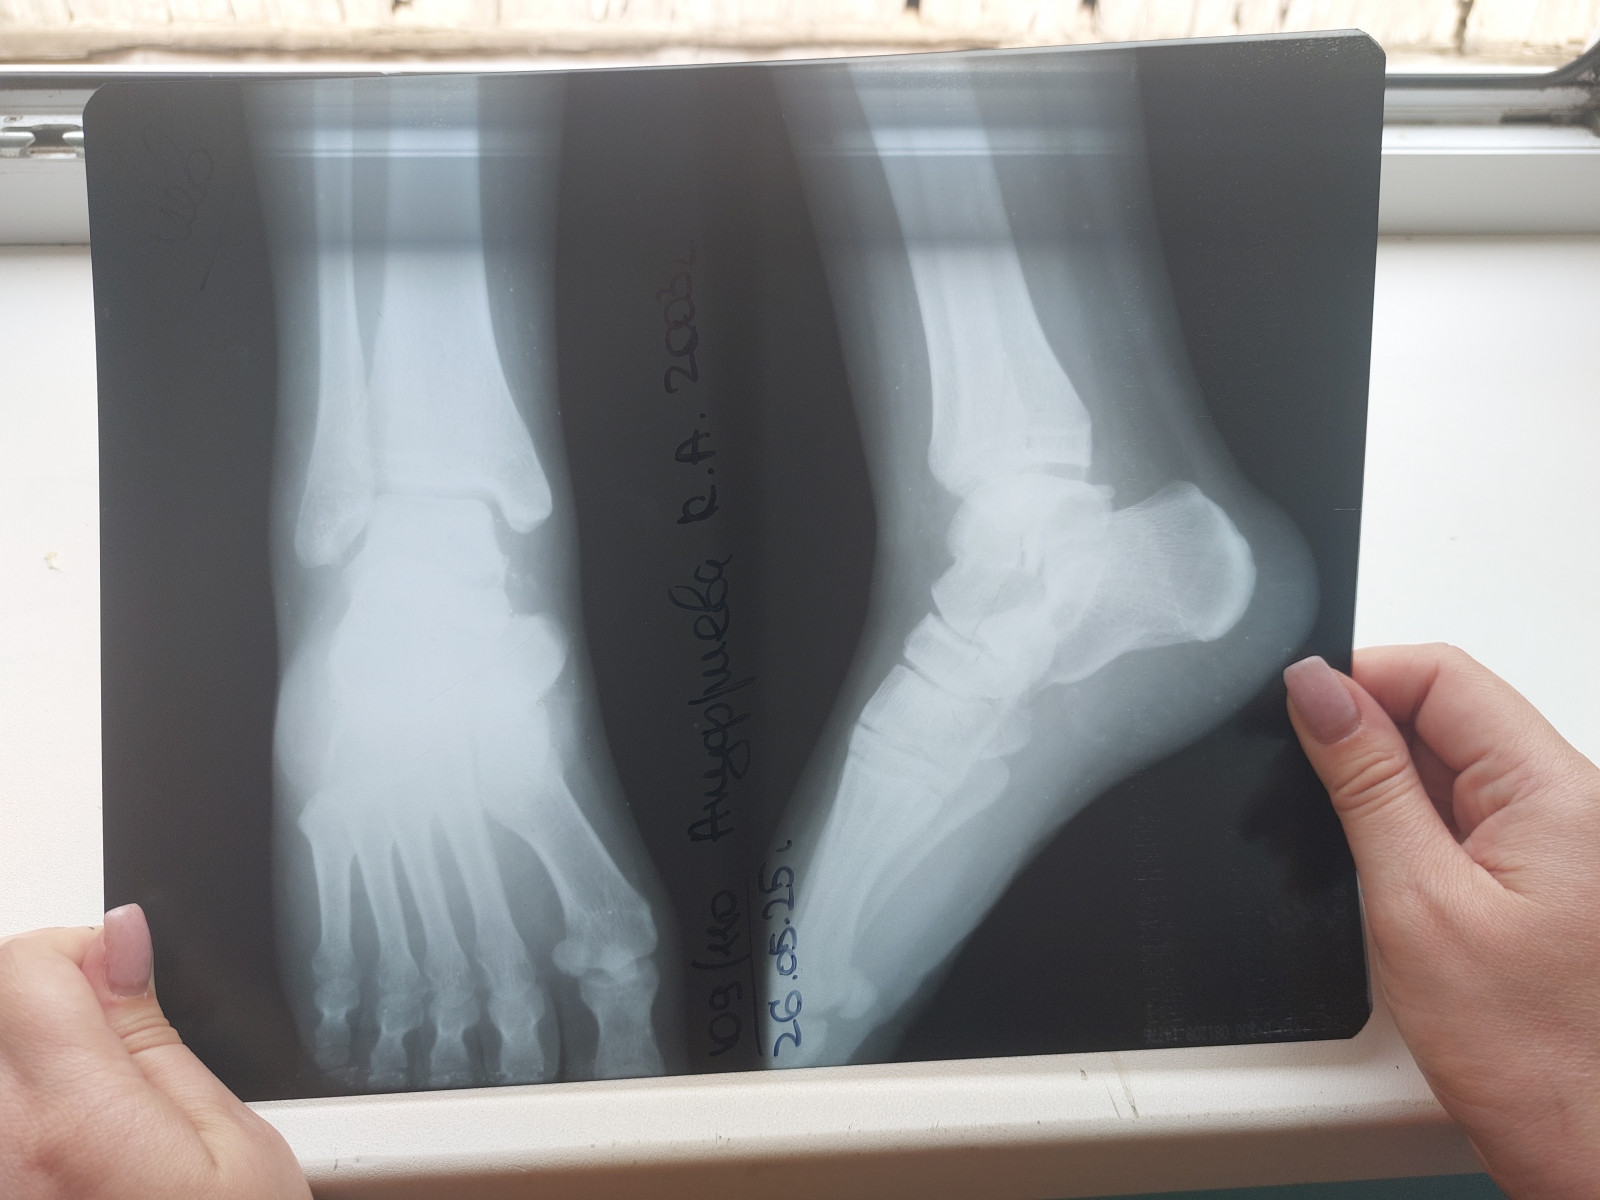

Добрый день, 21.04.25 сломала ногу, перелом голеностопного сустава без смещения. Наложили гипс, спустя 2.5 недели гипс сменили на ортез. Спустя еще неделю начала наступать на ногу и ходить в ортезе, все хорошо. После ортез сняла и ходила без него 3 дня, дискомфорт есть, но не критично. 26.05.2025 сделала повторный снимок. Подскажите пожалуйста можно ли уже наступать полноценно на ногу и выходить на работу?

Снимки прикрепляю